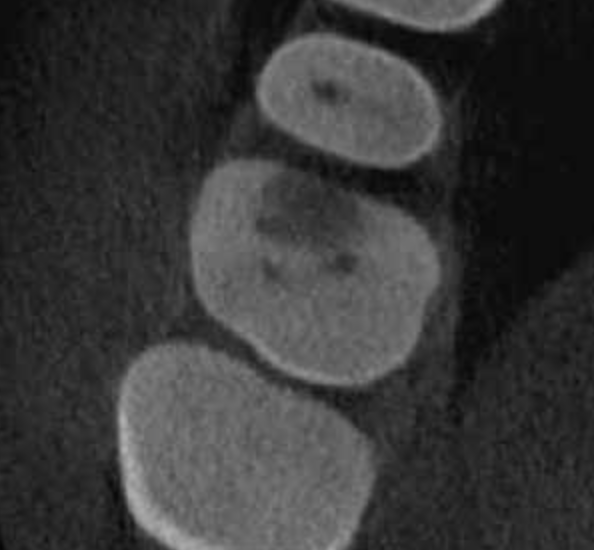

Diagnóstico de fisuras y fracturas

Vertical root fracture